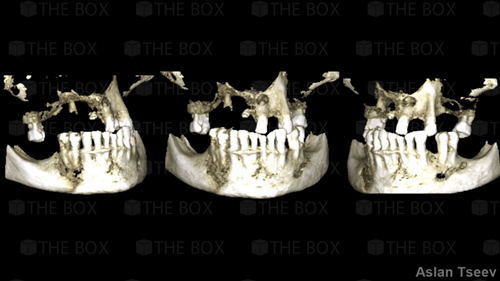

Infra bony defect one wall defect follow up 18 months show regeneration of buccal bone and interdental defect utilizing allograft bone substitute